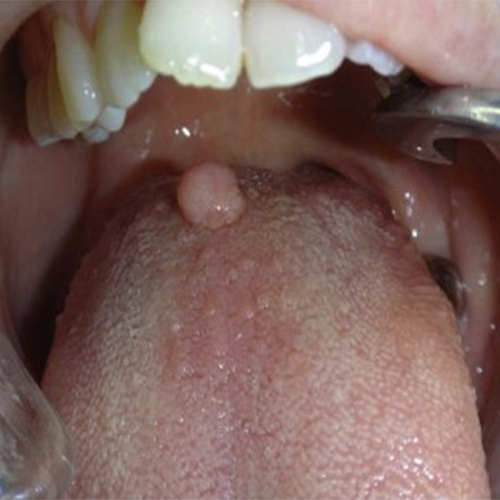

۹) اسکواموس پاپیلوما: یک ضایعه برجسته روی مخاط دهان است که محصول پرولیفراسیون خوشخیم سلولهای اپیتلیالی میباشد. علت آن ویروس پاپیلومای انسانی (HPV) است.

شایع ترین مکان آن مرز کام نرم و سخت است.

رنگ آن اغلب سفید و گاهی صورتی است. خیلی بزرگ نمیشود و صد البته در جوانان بیشتر رخ میدهد.

تصاویری از تومورهای دهانی